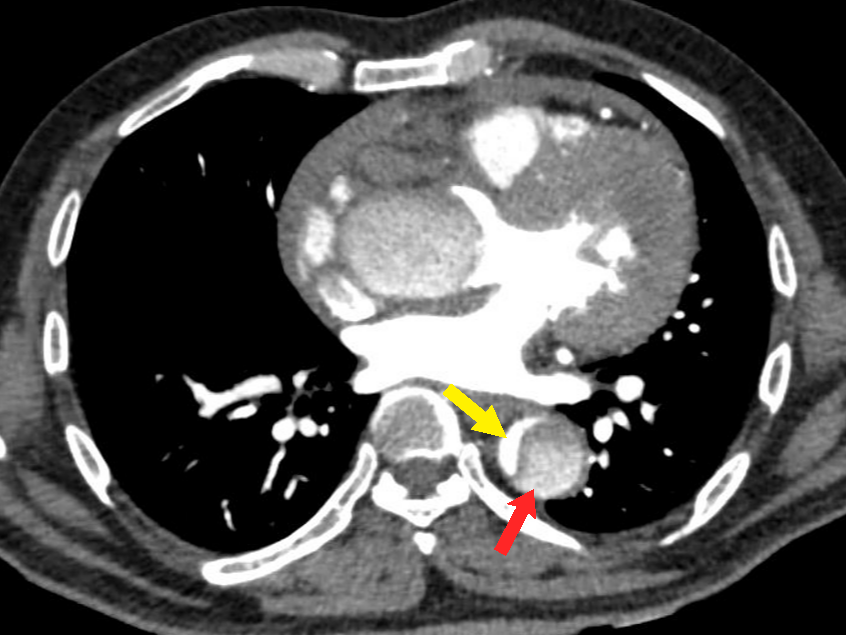

Figure 10 a-b Intramural hematoma. (a) Axial non-contrast CT thorax image in a case of thoracic aortic aneurysm (white asterisk) shows a crescentic thickening of high attenuation within the wall of the descending thoracic aorta (red arrow). Intimal calcifications are seen displaced inwards (yellow arrows). (b) A contrast-enhanced CT thorax image of the same patient shows no enhancement of the IMH. Bilateral pleural effusions are also seen in both images (a) & (b).